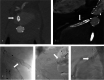

Objective: To present a case series of spontaneous structural failure of bridging stentgrafts (BSGs) after branched endovascular aortic repair (bEVAR), as well as their failure types and their detection. While bEVAR is a safe and effective procedure, one main limitation is the reintervention rate associated with the BSGs. Structural failure of BSGs, defined as fabric disruption, stent fracture with leak or complete separation is a major cause for reinterventions and difficult to detect in computed tomography angiography (CTA).

Results: Twenty-three BSG failures were detected in 12 patients with only 43% directly identified in CTA, after a mean of 21.4 months after implantation. The BSGs were Advanta (n = 4), E-Ventus (n = 16) and BeGraft (n = 3) in 10 renal, 9 superior mesenteric, and 4 celiac branches. Religning with another BSG was successful in 20/22 cases, one BSG failure necessitated renal branch embolization (organ loss), and one mesenteric bypass surgery. Two reintervention-related mortalities occurred.

Conclusion: Structural failure of BSGs is a serious limitation for bEVAR, which can result in high reintervention rates and serious complications. BSG failure typically occurs in single-layer types and events are clustered in patients. The necessary reinterventions carry serious morbidity and mortality. Since the use as BSG in bEVAR is off-label with all current BSG manufacturers, caution is advised regarding patient-informed consent.